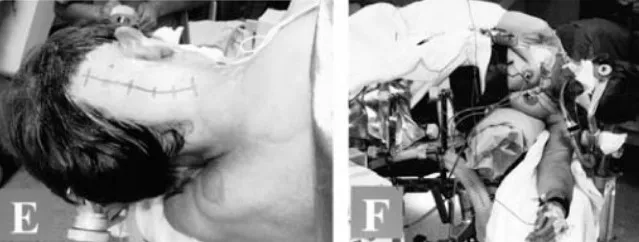

巴教授采取了左側(cè)臥位,讓Belle置于左側(cè)側(cè)位,頭部彎曲并旋轉(zhuǎn)到右側(cè)。手術(shù)術(shù)中應(yīng)用軀體感覺(jué)和聽(tīng)覺(jué)誘發(fā)電位的連續(xù)監(jiān)測(cè)。側(cè)枕下開(kāi)顱術(shù)延伸至遠(yuǎn)側(cè)乙狀竇和C1半椎板切除術(shù),枕骨大孔的背外側(cè)邊緣逐漸被鉆開(kāi),并對(duì)腦干和脊髓進(jìn)行了精心護(hù)理。

枕骨大孔腦膜瘤 圖片1

枕骨大孔腦膜瘤 圖片2

術(shù)中及腫瘤切除后的硬膜內(nèi)部位

枕骨大孔腦膜瘤手術(shù)圖片

手術(shù)切口及手術(shù)時(shí)病人的位置